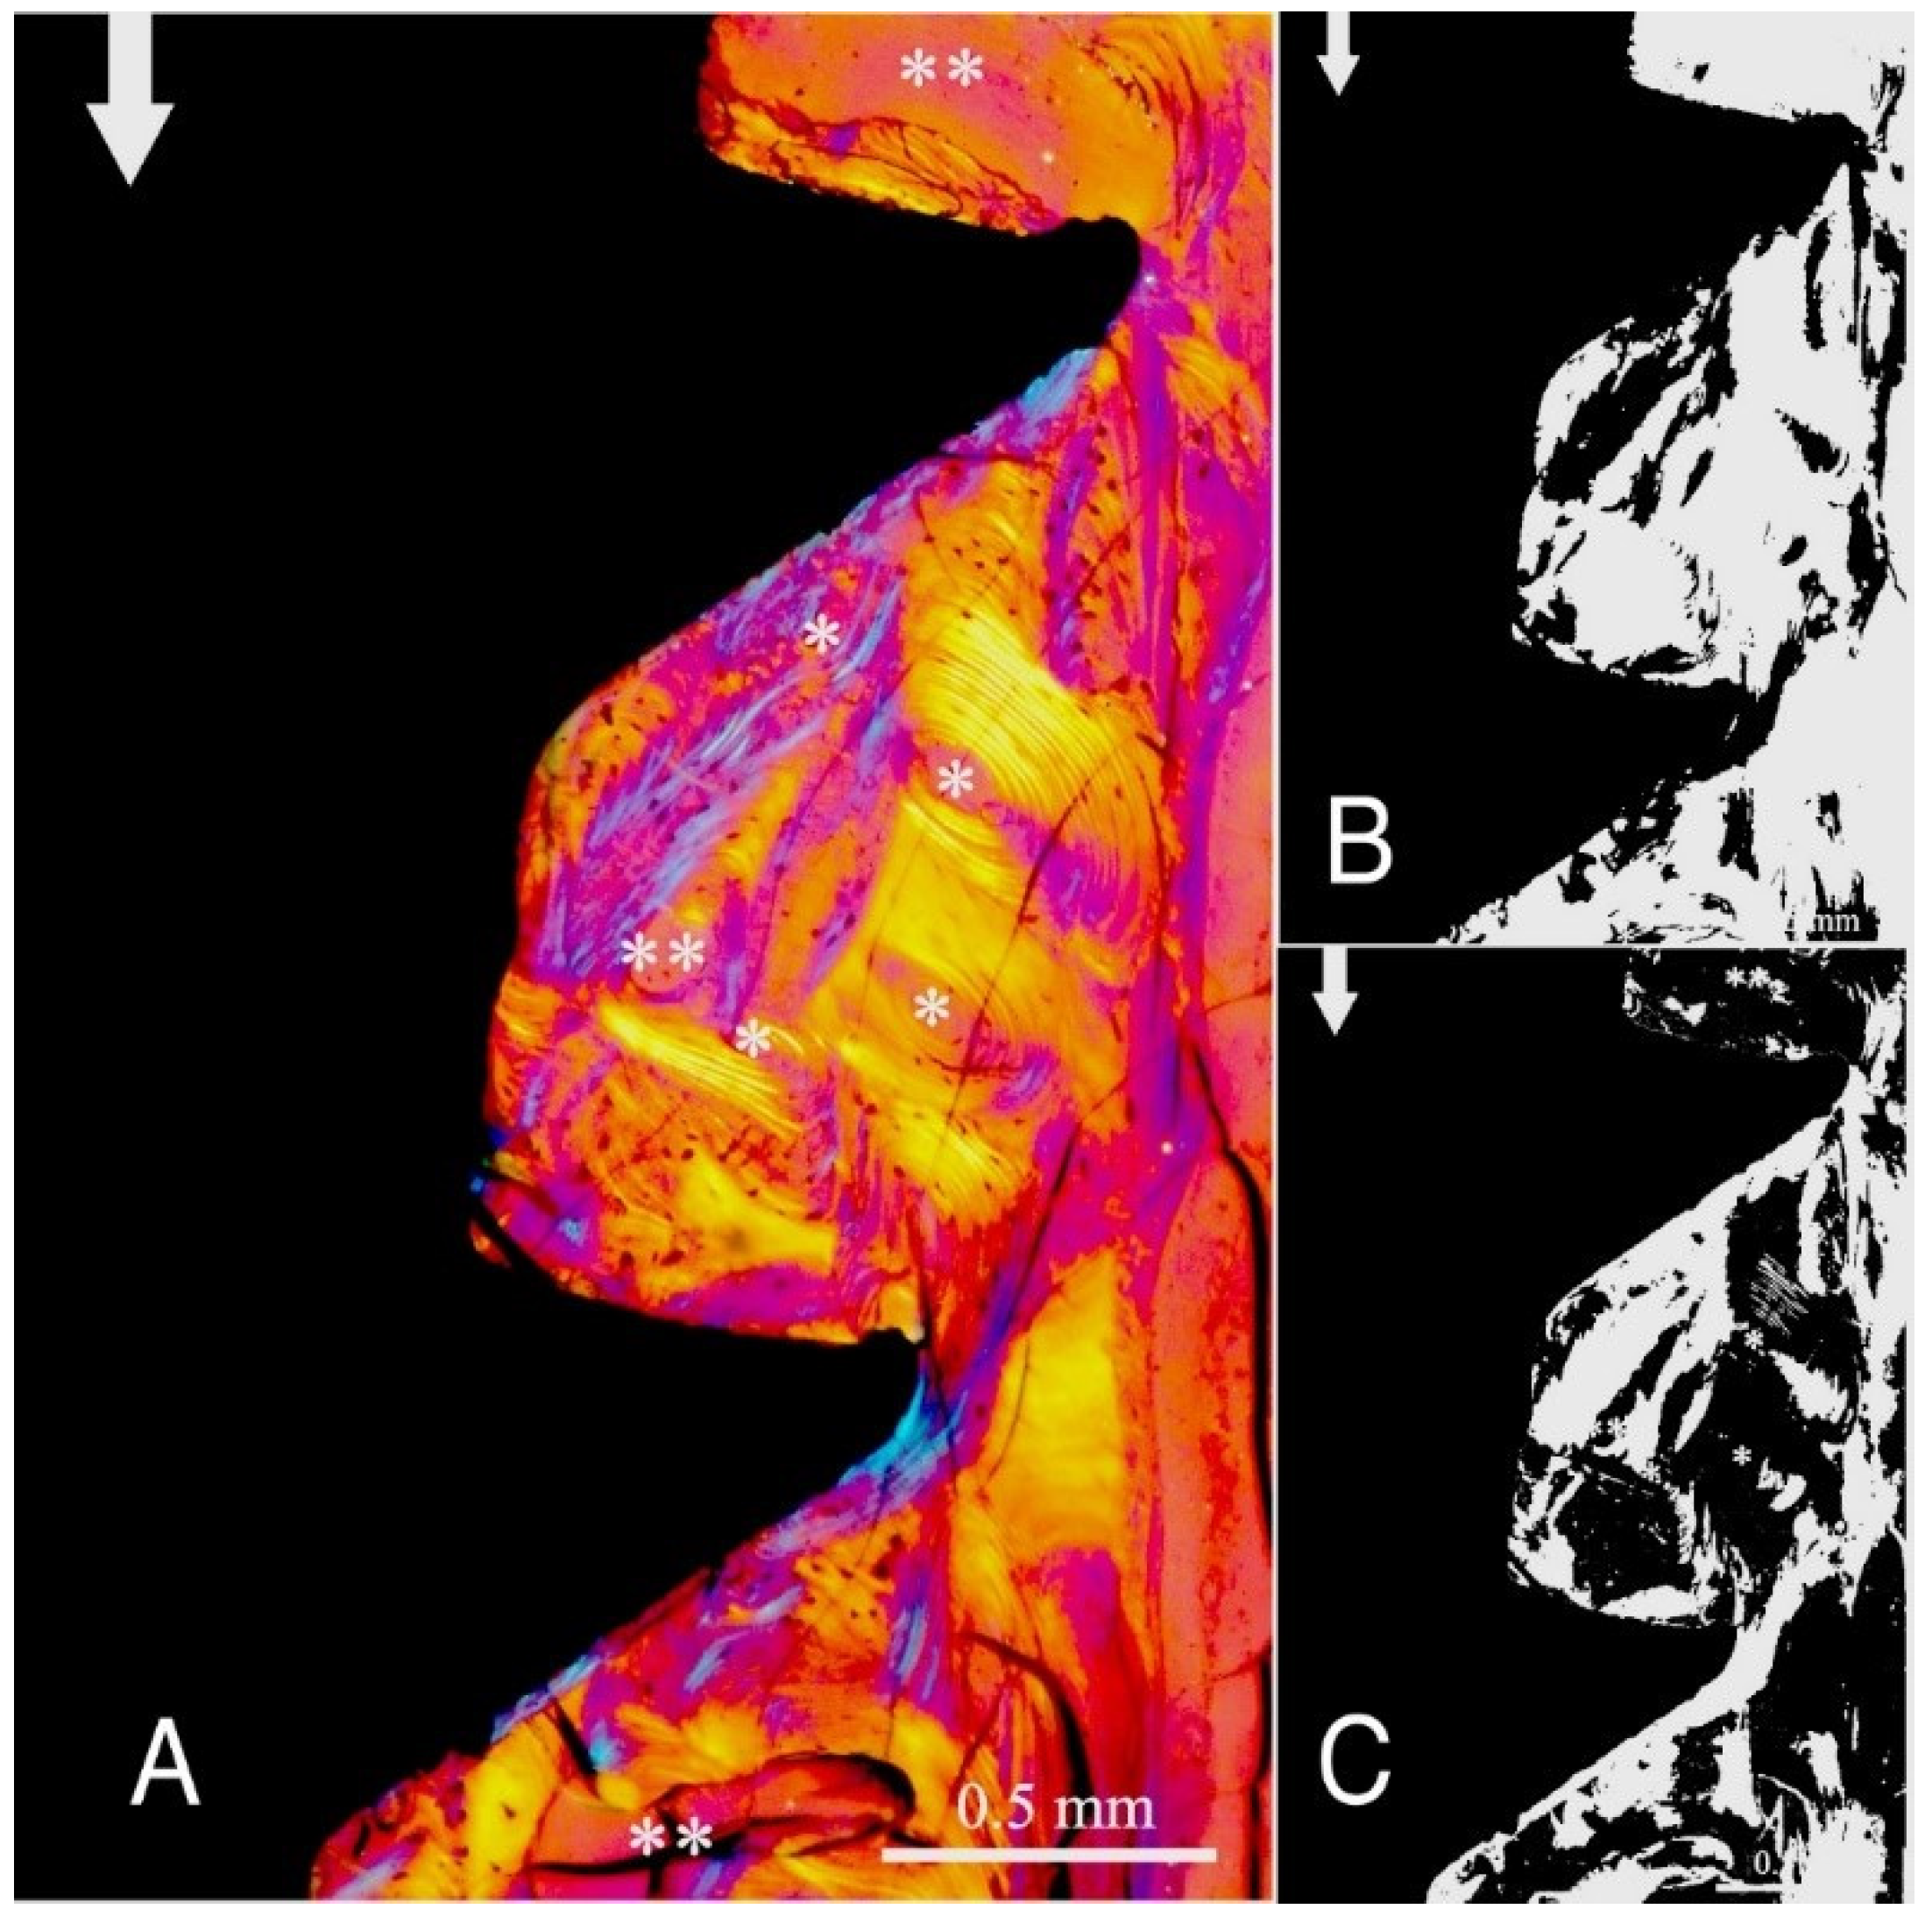

Figure 1. (A) Circularly polarized light microscopy image of unstained section for bone collagen fibre orientation evaluation around the implant threads of group A (see Table 1 for groups’ identification according to implant thread profile parameters). Mag. 100×. White arrows: main direction of occlusal load; *, **: Havers canals. The collagen fibre orientation of the bone adjacent to the lower flank and near the tip of the ‘V’-shaped threads is predominantly transverse (white-blue), while in other areas, it is longitudinal (yellow-orange). (B,C) Computer separations of transverse (B) and longitudinal (C) bone collagen fibre orientations.

The study groups design used in this study is displayed in Table 1 and it is comprehensively described in Section 4 (Materials and Methods). The relative amount and the differences between the transverse and longitudinal collagen fibres in the bone samples of each group are summarized in Table 2 and illustrated in Figure 1, Figure 2, Figure 3, Figure 4, Figure 5 and Figure 6 and Figure S1. Of further note, for group A (Figure 1) and group B (Figure 2), the transversely oriented collagen fibres were mainly seen adjacent to the lower flank of the thread of the dental implants, while the longitudinally oriented collagen fibres were more spread throughout the bone tissue. Figure 3, Figure 4, Figure 5 and Figure 6 illustrate the bone samples for groups C to F, respectively.